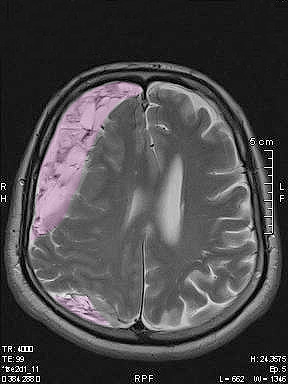

Subdural

Τα χρόνια υποσκληρίδια αιματώματα είναι αιματώματα τα οποία αναπτύσσονται στην επιφάνεια του εγκεφάλου καθυστερημένα (εβδομάδες έως και μήνες) μετά από μια, συνήθως ήπια, κάκωση της κεφαλής, κυρίως σε ασθενείς ηλικιωμένους, με διαταραχές της πήξεως του αίματος ή λαμβάνοντες αντιπηκτική ή αντιαιμοπεταλιακή φαρμακευτική αγωγή όπως η ασπιρίνη. Η ανάπτυξή τους είναι αργή και το ίδιο ισχύει για τα ποικίλα συμπτώματά τους. Η θεραπεία στα μεγάλα ή προκαλούντα συμπτώματα χρόνια υποσκληρίδια αιματώματα είναι κατά κανόνα χειρουργική με κρανιοανάτρηση ή μικρή κρανιοτομία και παροχέτευση του αιματώματος.

Αξονική ή μαγνητική τομογραφία εγκεφάλου. Σε ορισμένες περιπτώσεις τα χρόνια υποσκληρίδια αιματώματα μπορεί έχουν την ίδια πυκνότητα στην απεικόνιση με το εγκεφαλικό παρέγχυμα ή να βρίσκονται ακόμη σε πρώϊμο στάδιο ανάπτυξης όσον αφορά στο μέγεθος και τη σύσταση, και αυτό μπορεί να καταστήσει την διάγνωση πιο δύσκολη.